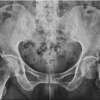

A 66-year-old female presented to our clinic with painless, limited range of motion (ROM) in her left hip, and pain in her left knee that had begun to affect her daily activities. She first noticed limitations in ROM in her early 30s and she reported that by age 40, her ROM was essentially zero. Past medical history also included bilateral knee arthritis and daily tobacco use. She reported having her hip examined as a child but did not recall receiving a formal diagnosis. Physical examination revealed increased lumbar lordosis during ambulation with compensatory hip hiking, left leg shortening with a hip internal rotation, and flexion contracture with no active and passive hip ROM. A pelvic radiograph revealed left hip fusion, severe dysplasia, and complete obliteration of the joint space (Fig. 1). Review of prior radiographs revealed arthritic changes in her left knee as well. Computed tomography (CT) reconstruction was performed to evaluate the patient’s acetabular bone stock and native femoral version, demonstrating a thinned native posterior wall and increased femoral anteversion compared to the contralateral hip (Fig. 2). The patient consented to undergo hip fusion takedown to primary THA to regain hip ROM.